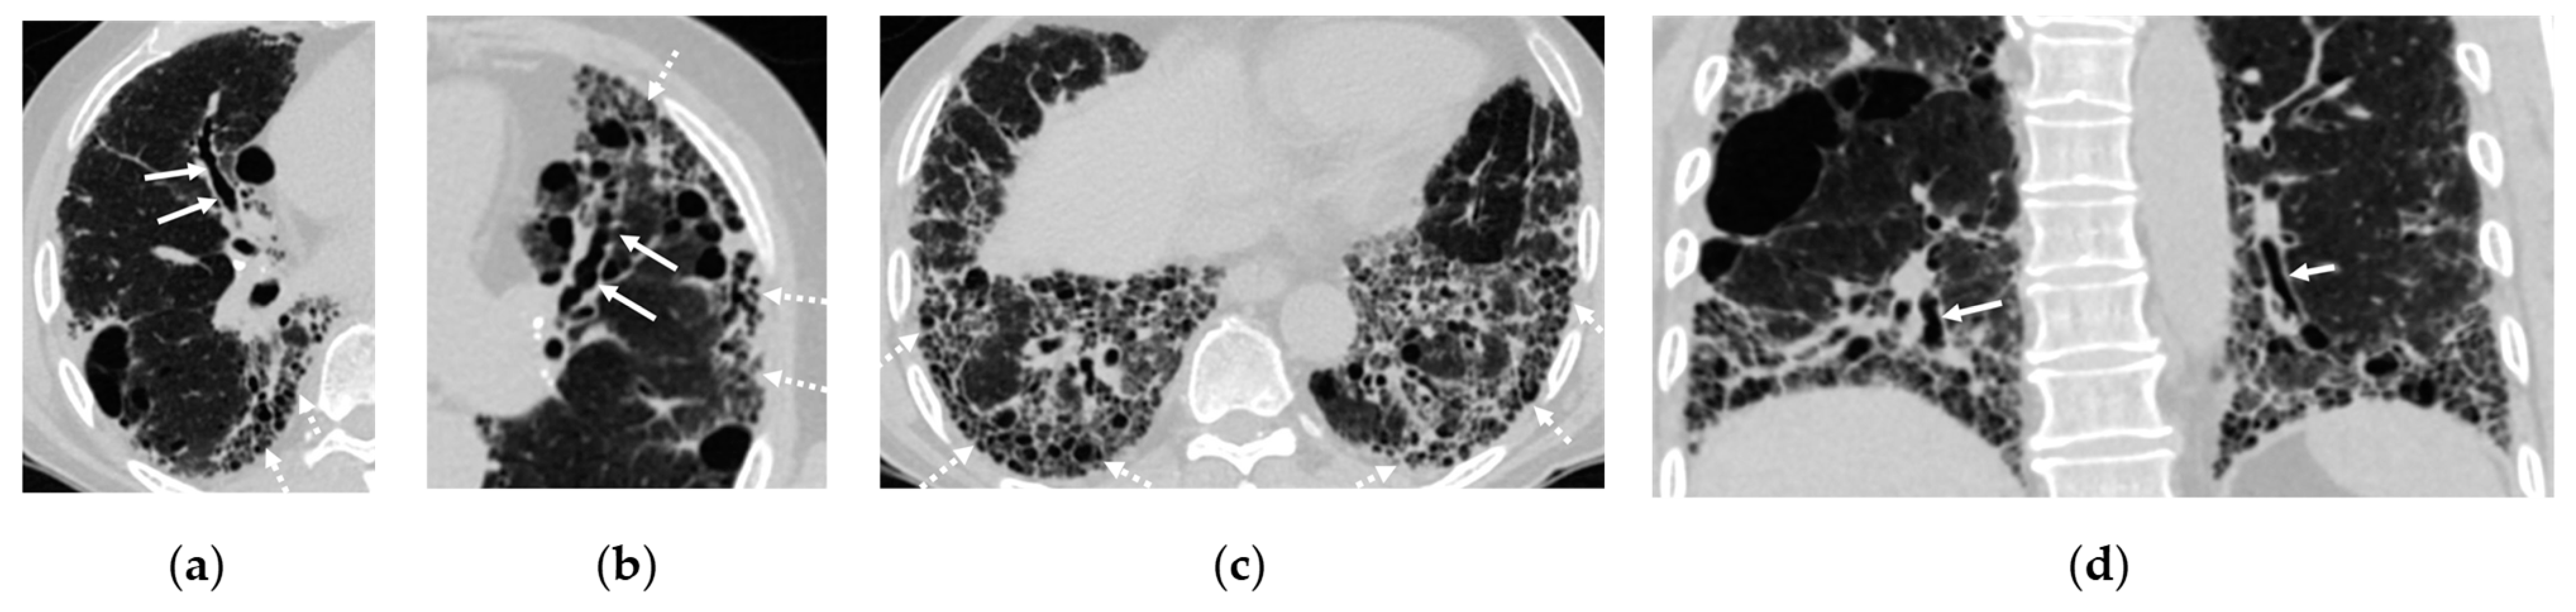

3.4. Cystic Lung Disease